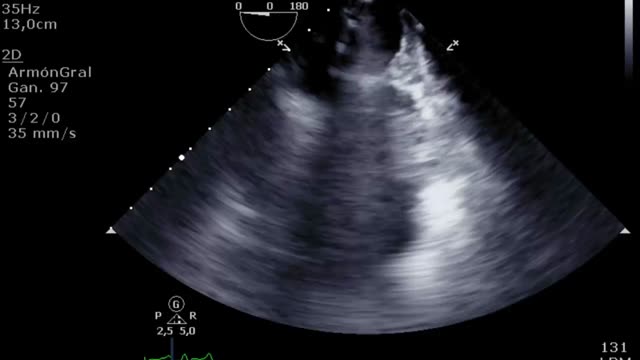

En la evaluación para el implante de una ECMO VV otro factor esencial es la función del ventrículo derecho (VD). Muchos pacientes con síndrome de distrés respiratorio agudo grave presentan hipertensión pulmonar y disfunción del VD en relación con la hipoxia, la hipercapnia, el aumento de la presión de las vías aéreas y la ventilación mecánica. La ECMO VV, al corregir la hipoxia y la hipercapnia, disminuye la poscarga y puede mejorar la función del VD de manera que se corrija la inestabilidad hemodinámica. En caso de presentar una disfunción ventricular derecha significativa será importante realizar un seguimiento ecocardiográfico y, si se perpetúa la situación de shock y no mejoran los parámetros ecocardiográficos a pesar de la ECMO VV, habría que plantear un cambio de estrategia a un VA o veno-arteria-vena. Para la evaluación de la disfunción del VD valoraremos: desplazamiento sistólico del plano del anillo tricuspídeo<16mm, onda S’<10cm/s, fracción de acortamiento<35%, relación área telediastólica VD/VI>0,6 significativa y >1 grave o aplanamiento/abombamiento (en forma de «D») del septo interventricular tanto en sístole como en diástole (suplementario 1). Esta interdependencia se puede cuantificar a través del índice de excentricidad ventricular, que es el cociente entre el diámetro septo-cara inferior y cara anterior-cara inferior en sístole y diástole, siendo su valor normal=118.

El destete supone un proceso de descenso gradual (500ml cada 15-20min) del soporte de la ECMO VA de manera que se restablece progresivamente la precarga en el corazón. Para ello el paciente debe estar adecuadamente anticoagulado. Evaluaremos la repercusión hemodinámica (PVC, PAM y diferencial, SvO2, SatO2) y ecocardiográfica (FEVI, IVT, onda E, onda E’ o S’ del anillo mitral lateral) que tiene hasta un nivel (normalmente 1-1,5l/min) que nos indique que el paciente puede tolerar la retirada de la asistencia. Durante esta, evaluaremos que mantiene e incluso aumenta la FEVI por encima del 25-30%, la IVT por encima de 10cm y la onda S’ de más de 6cm/s (fig. 5 y suplementario 22). Junto con ello, también evaluaremos el comportamiento de las cavidades derechas (desplazamiento sistólico del plano del anillo tricuspídeo>16cm, S’>10cm/s y tamaño VD) y la posible aparición de signos de hipertensión pulmonar (aumento de la velocidad pico de la insuficiencia tricuspídea) que predigan un fracaso de VD38–40.

Evaluación ecocardiográfica de destete de paciente con ECMO VA. Ecografía transtorácica e integral velocidad-tiempo (IVT) del tracto de salida del ventrículo izquierdo al reducir flujo (A: 3L/min, B: 2,5L/min, C: 2L/min) de ECMO VA. Obsérvese el aumento del tamaño de la IVT y consecuentemente del volumen sistólico y del gasto cardiaco.